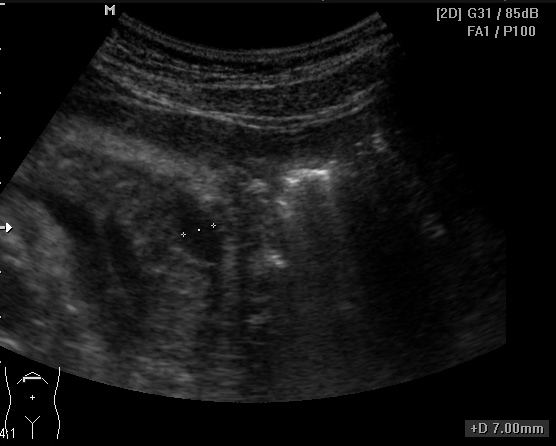

Женщина, 31 год, с умеренной болью в эпигастрии. Беспокоит боль периодически в течение 2 месяцев, усилилась примерно 2 недели назад. ОАК, ОАМ, БАК в норме, температура тела в норме. В малом тазу большое кол-во жидкости мелкодисперстной, особенно кпереди от матки (не сохранила ни скан, ни видео).

в проекции хвоста поджелудочной железы

Из того, что понятно: есть киста хвоста поджелудочной железы, жидкость в малом тазу (мелкодисперстная) и немного в брюшной полости (с нитями фибрина), кисты правого яичника.

1. По передней поверхности поджелудочной железы жидкость (1-ое видео и 3-ий сверху снимок) или мне кажется?

Из представленных Вами материалов. Пересматриваю раз за разом первый клип - отек парапанкреатической ткани. Исключайте о.панкреатит.